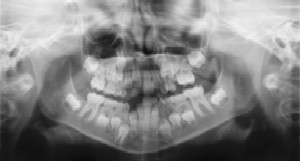

Radiographs (X-Rays) are a vital and necessary part of your child’s dental diagnostic process. Without them, certain dental conditions can and will be missed.

Radiographs detect much more than cavities. For example, radiographs may be needed to survey erupting teeth, diagnose bone diseases, evaluate the results of an injury, or plan orthodontic treatment. Radiographs allow dentists to diagnose and treat health conditions that cannot be detected during a clinical examination. If dental problems are found and treated early, dental care is more comfortable for your child and more affordable for you.

The American Academy of Pediatric Dentistry recommends radiographs and examinations every six months for children with a high risk of tooth decay. On average, most pediatric dentists request radiographs approximately once a year. Approximately every 3 years, it is a good idea to obtain a complete set of radiographs, either a panoramic and bitewings or periapicals and bitewings.

Pediatric dentists are particularly careful to minimize the exposure of

their patients to radiation. With contemporary safeguards, the amount of

radiation received in a dental X-ray examination is extremely small. The

risk is negligible. In fact, the dental radiographs represent a far smaller risk

than an undetected and untreated dental problem. Lead body aprons and

shields will protect your child. Today’s equipment filters out unnecessary

x-rays and restricts the x-ray beam to the area of interest. High-speed film

and proper shielding assure that your child receives a minimal amount of

radiation exposure.